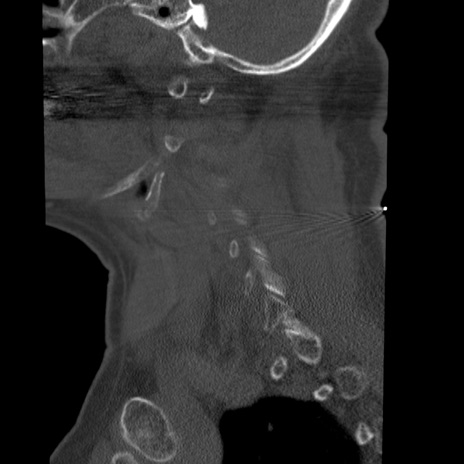

症例50 頚椎CT(矢状断像)

【症例】60歳代女性

【主訴】後頭部〜右後頸部にかけての痛み

【現病歴】本日飲食店でコーヒーを飲んでいたところ、突然後頭部〜右後頸部にかけて痛みが出現し、右上肢の感覚障害を伴ったため救急要請。

【身体所見】脳神経学的に明らかな異常所見を認めず。右上肢に軽度の感覚障害あり。

横断像